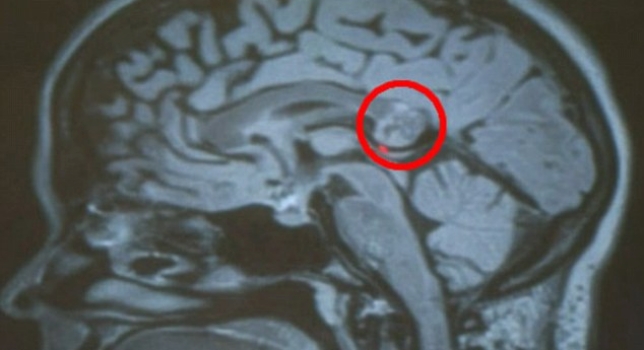

Yamini Karanam es una mujer estadounidense de 26 años de edad que fue sometida a una operación para que le extirparan un supuesto tumor que tenía en el cerebro. Sin embargo, los médicos jamás imaginaron que encontrarían algo fuera de lo común : el gemelo embrionario de su paciente.

Hrayr Shahinian, cirujano que encabezó el equipo que realizó la intervención quirúrgica en el Skukkbase Institute de Los Ángeles, se mostró sorprendido ante el hallazgo de este embrión que nunca llegó a desarrollarse aunque presentaba huesos, pelo y dientes. "Este es mi segundo caso, y eso que probablemente habré extirpado entre 7.000 u 8.000 tumores cerebrales", explicó.

Karanam, una estudiante de doctarado de la Universidad de Indiana, tenía dificultades de comprensión de lectura además de tener problemas para escuchar claramente. Después de una serie de exámenes, los médicos determinaron que había un tumor cerebral. La paciente se recuperó tras la operación y decidió guardar los restos de su hermano gemelo en un frasco.